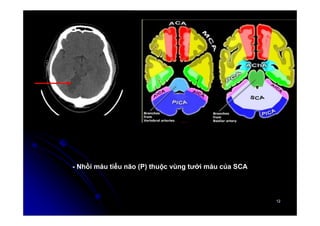

- Nhồi máu tiểu não (P) thuộc vùng tưới máu của SCA